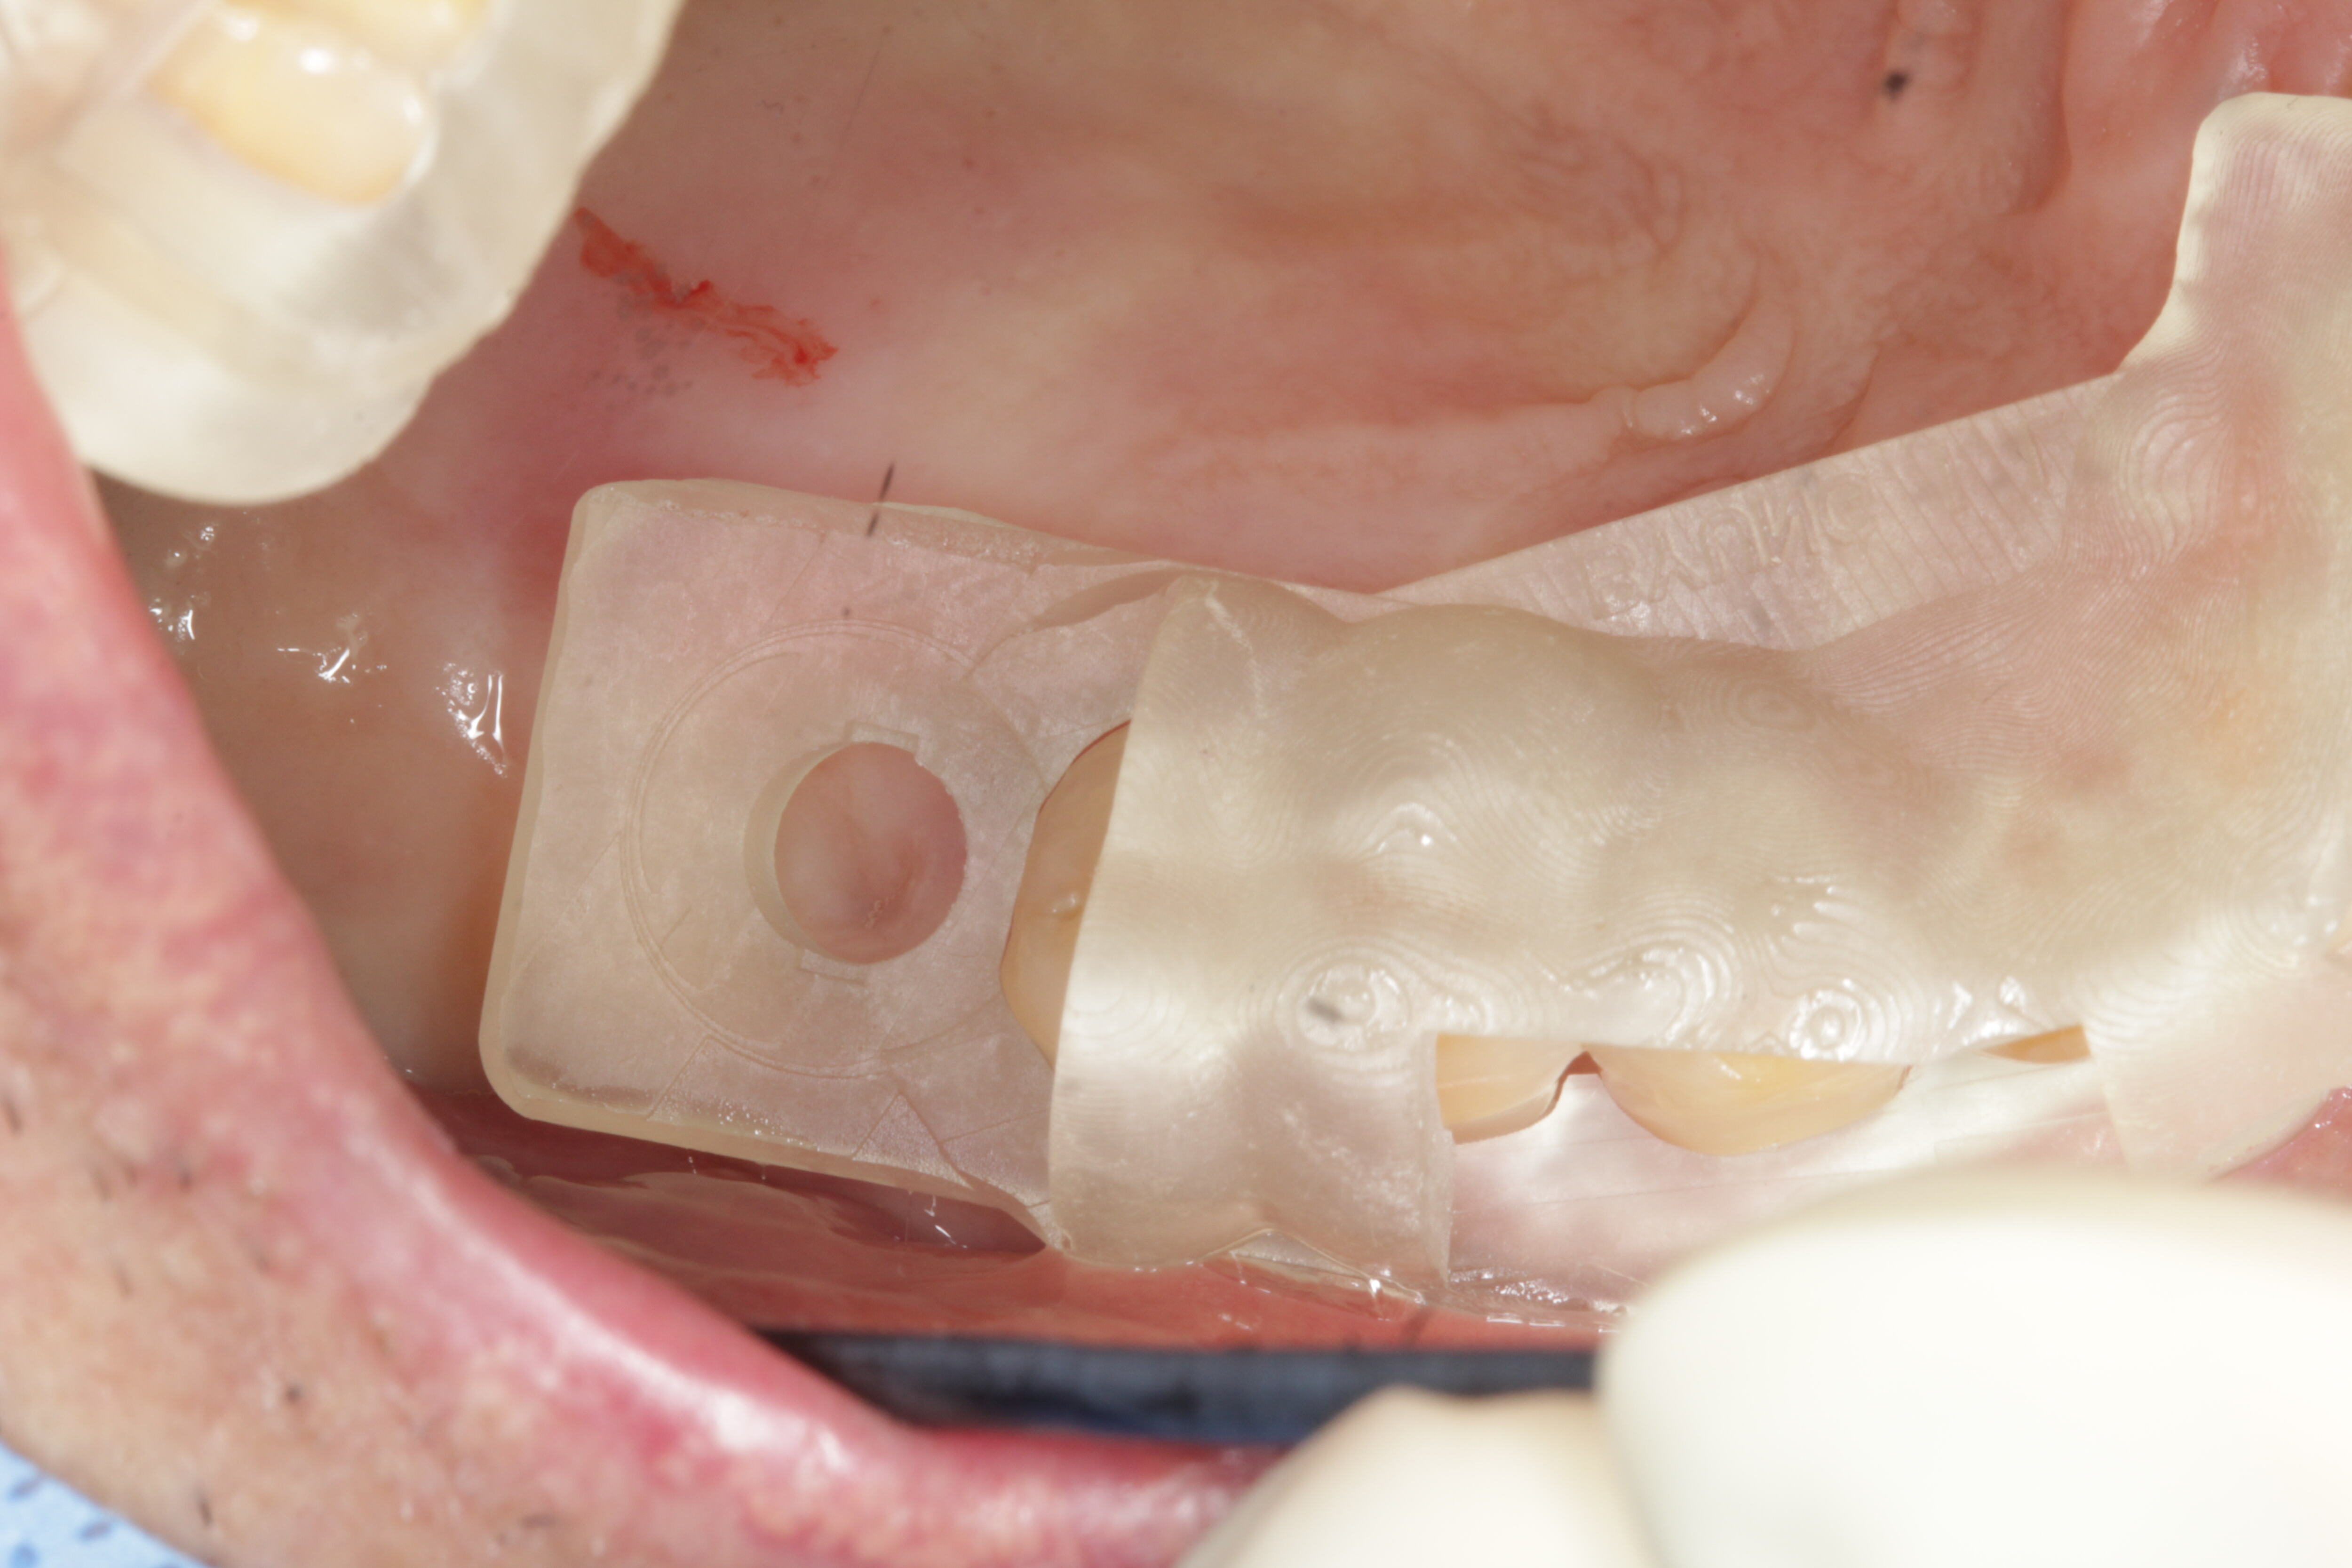

⋅ Guided Surgery

⋅ Guided Surgery

Guided Surgery Case 1

Guided Surgery Case 1